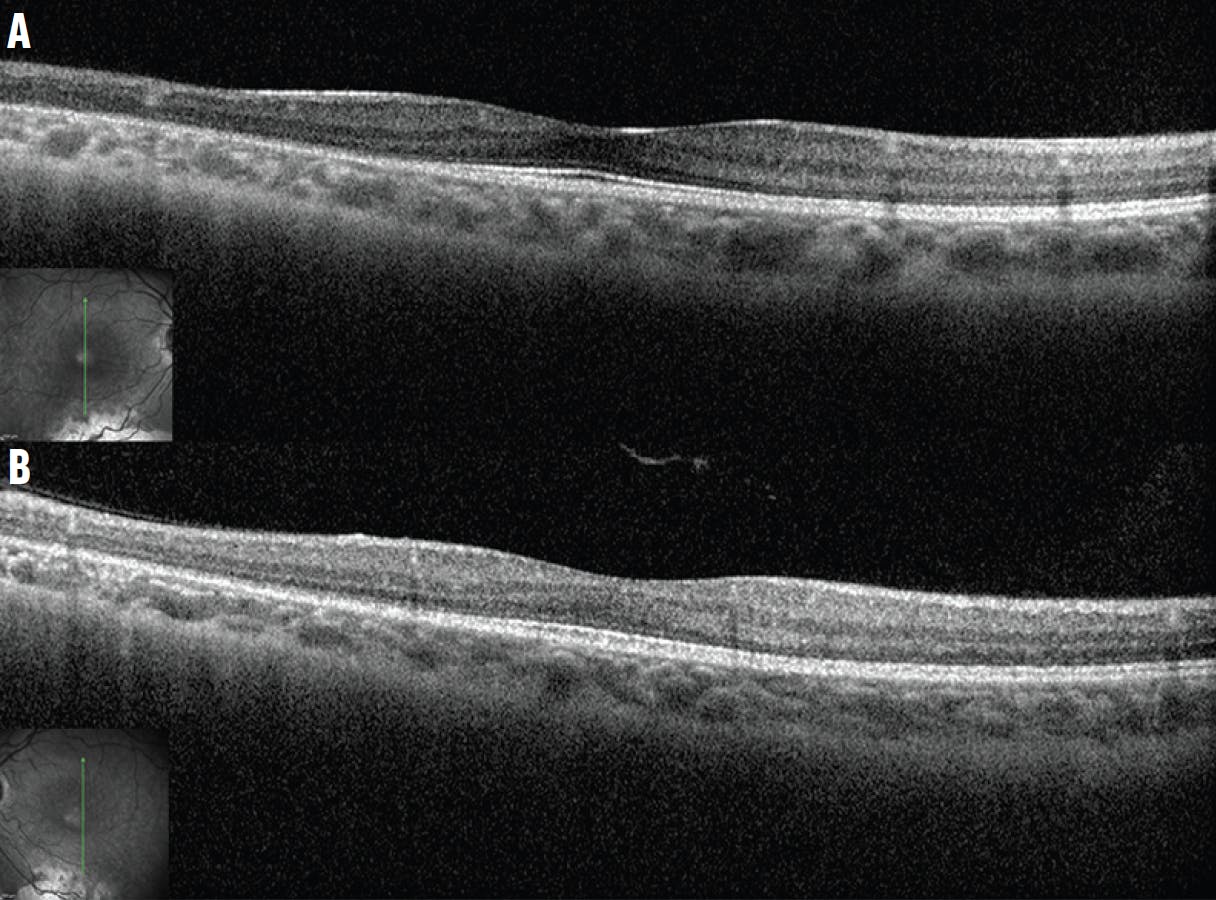

An 8-year-old boy was referred to the office with problems with his night vision. The patient’s mother reported that the child prefers brighter rooms. The patient had a normal birth history and no past ocular or family history. On initial examination, the patient's BCVA was 20/25 OD and 20/30 OS. The anterior segment examination was normal in each eye. The fundus examination revealed diffuse and discrete whitish flecks with macular sparing in each eye (Figure 4). OCT imaging located the lesions in the zone of interaction between the photoreceptor inner and outer segment and the apical retinal pigment epithelium (RPE, Figure 5). Fundus autofluorescence imaging showed small flecks of hyperautofluorescence in each eye, which may correlate to the spots on the fundus photographs. Full-field electroretinogram (ERG) testing demonstrated diminished scotopic responses that markedly improved to normal after prolonged dark adaptation.

Figure 5. OCT imaging shows the lesions in the zone of interaction between the photoreceptor inner and outer segment and the apical RPE (white arrows) in the right (A) and left (B) eyes.

The disease is characterized by numerous small white dots from the midperipheral to peripheral retina, without vascular or optic nerve abnormalities. The deposits are localized between the outer limiting membrane and the outer aspect of the RPE on OCT.8,9 The shape and number of spots will vary with age and may even fade entirely.10 The presumed accumulation of cisretinol and cisretinyl esters in the RPE due to 11-cis-retinol dehydrogenase deficiency may be responsible for the formation of the white dots seen in RDH5 mutation-associated fundus albipunctatus.11